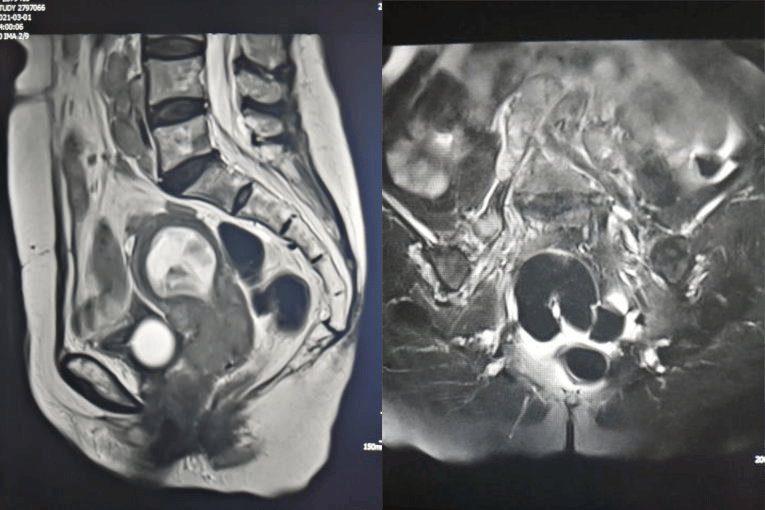

腹膜后弥漫性淋巴瘤。肿瘤弥漫性浸润腹膜后脂肪间隙及双肾、直肠系膜,包绕主动脉及下腔静脉